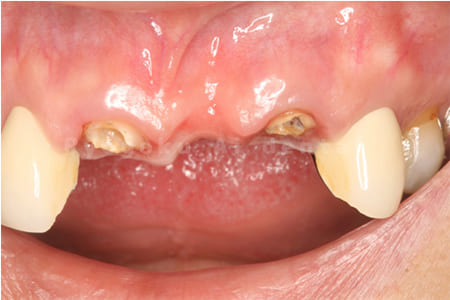

前歯の腫れが治らないとのことでご来院された患者様です。虫歯も大きかったですが、手術を行い、歯牙の保存を行いました。現在も問題なく経過しております。

- クラウンレングスニング、ポンティックシールド、セラミッククラウン修復

- 原因

- 重度カリエス

- 治療日数

- 10ヶ月

- 治療内容

- 治療費用

- 約1,500,000円